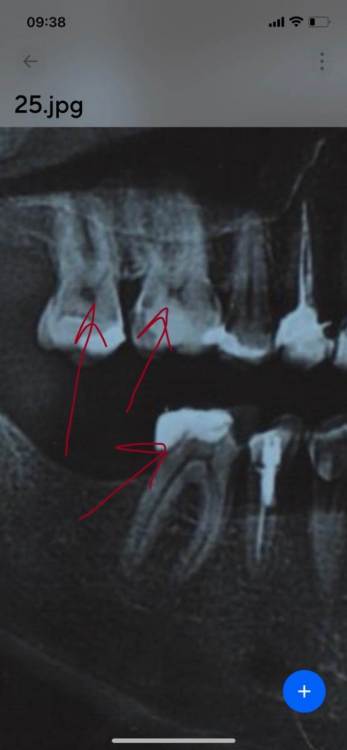

seogud Опубликовано 13 мая, 2022 Поделиться Опубликовано 13 мая, 2022 Добрый день, не могу понять , из за чего у меня тупая боль, панорамный снимок зубов прилагаю Ссылка на комментарий

red_butler Опубликовано 15 мая, 2022 Поделиться Опубликовано 15 мая, 2022 тут кандидатов на "болит" с десяток Ссылка на комментарий

seogud Опубликовано 15 мая, 2022 Автор Поделиться Опубликовано 15 мая, 2022 после приема пищи , с права на вверху и внизу Ссылка на комментарий

Гарриевич Опубликовано 4 июня, 2022 Поделиться Опубликовано 4 июня, 2022 Минимум 3 зуба которые надо проверить 1 1 Ссылка на комментарий